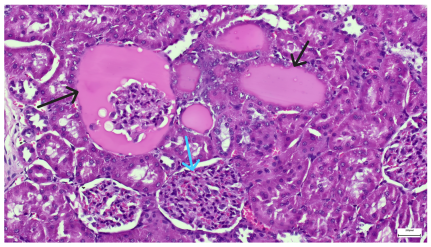

Table 4 below presents histological proof for renal damage in the G-IV group suffering from a dual metabolic impairment, albeit treated with statin.

Table 4.

Histological proof for renal damage in the diabetic-and-obese statin-treated group G-IV.

The histological extent of lesions suggests a definite inflammatory process in the renal matrix and glomeruli, but the extent of the disruptive process as resulting from an average nephron pool loss is limited. This is consistent with the limited duration of our experiment, with definite development of chronic kidney disease taking sometimes as long as 24 weeks. However, expecting this limited extent of damage, we chose a relatively short—proportionate—duration of statin treatment. Our results demonstrate a statistically significant higher retention of creatinine and urea in plasma—a reflection of the respective reduction in renal function—in every single experimental group (G-II to G-IV) in comparison to the control group G-I. The diabetic group G-III demonstrates the highest values for both creatinine and urea across the whole experiment population. The plasma concentrations of retention byproducts in both G-II and G-III are statistically significantly higher compared to the control G-I, indicating that each condition independently leads to important impairment in kidney function. The assumption of concurring actions in a model exhibiting obesity and diabetes simultaneously should translate into outcomes—renal and inflammatory—with values skewed from normality, the dimension of departure from the normal range at least as big as in any of the models exhibiting an individual condition.